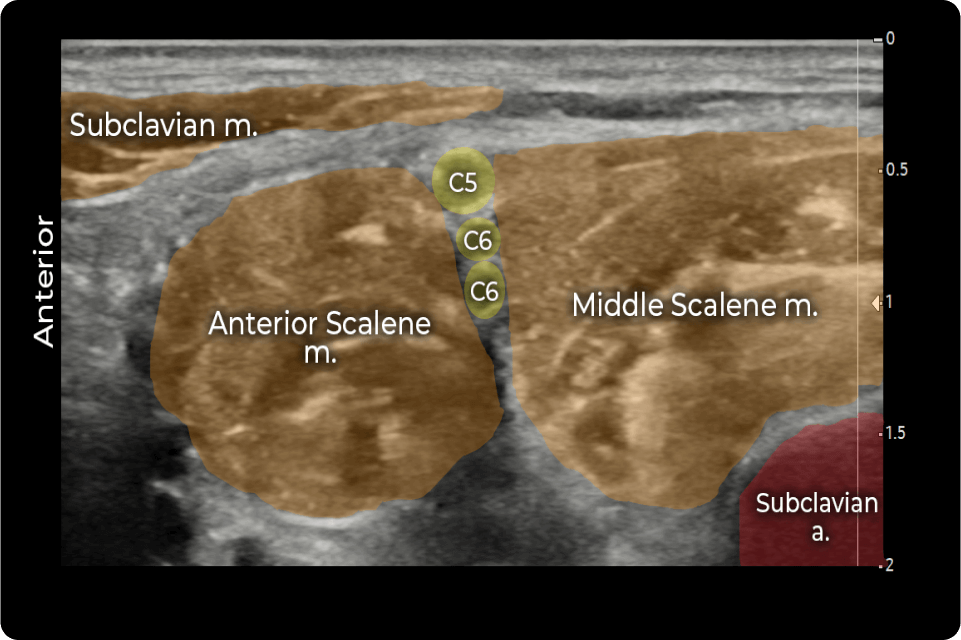

STEP 2: Visualize the C5 to C7 nerve roots

• Place an ultrasound probe on the patient’s neck superior to the clavicle to identify the interscalene brachial plexus between the anterior and middle scalene muscles

STEP 3: Perform ISBPNB with EXPAREL

• Insert a 20- to 22-gauge echogenic needle into the plane from lateral to medial until the tip is just lateral to the bottom of the interscalene brachial plexus

• Confirm needle position using nerve stimulation and hydrodissection

• Deposit EXPAREL between the anterior and middle scalene muscles until the infiltration around the brachial plexus is documented by ultrasound

ASM, anterior scalene muscle; C5 to C7, cervical nerve roots; DSN, dorsal scapular nerve; LCa, longus capitis muscle; LTN, long thoracic nerve; MSM, middle scalene muscle; RCR, rotator cuff repair; SCM, sternocleidomastoid; TSA, total shoulder arthroplasty; VA, vertebral artery.